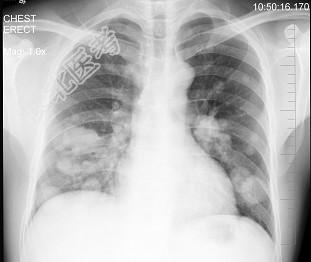

- 单项选择题男性,43岁, 胸闷、胸痛10余天,不咳嗽不发热, X线检查如图,最合理的诊断是 ( )

A、原发性肺癌

B、肺转移瘤

C、炎性假瘤

D、结核瘤

E、支气管扩张